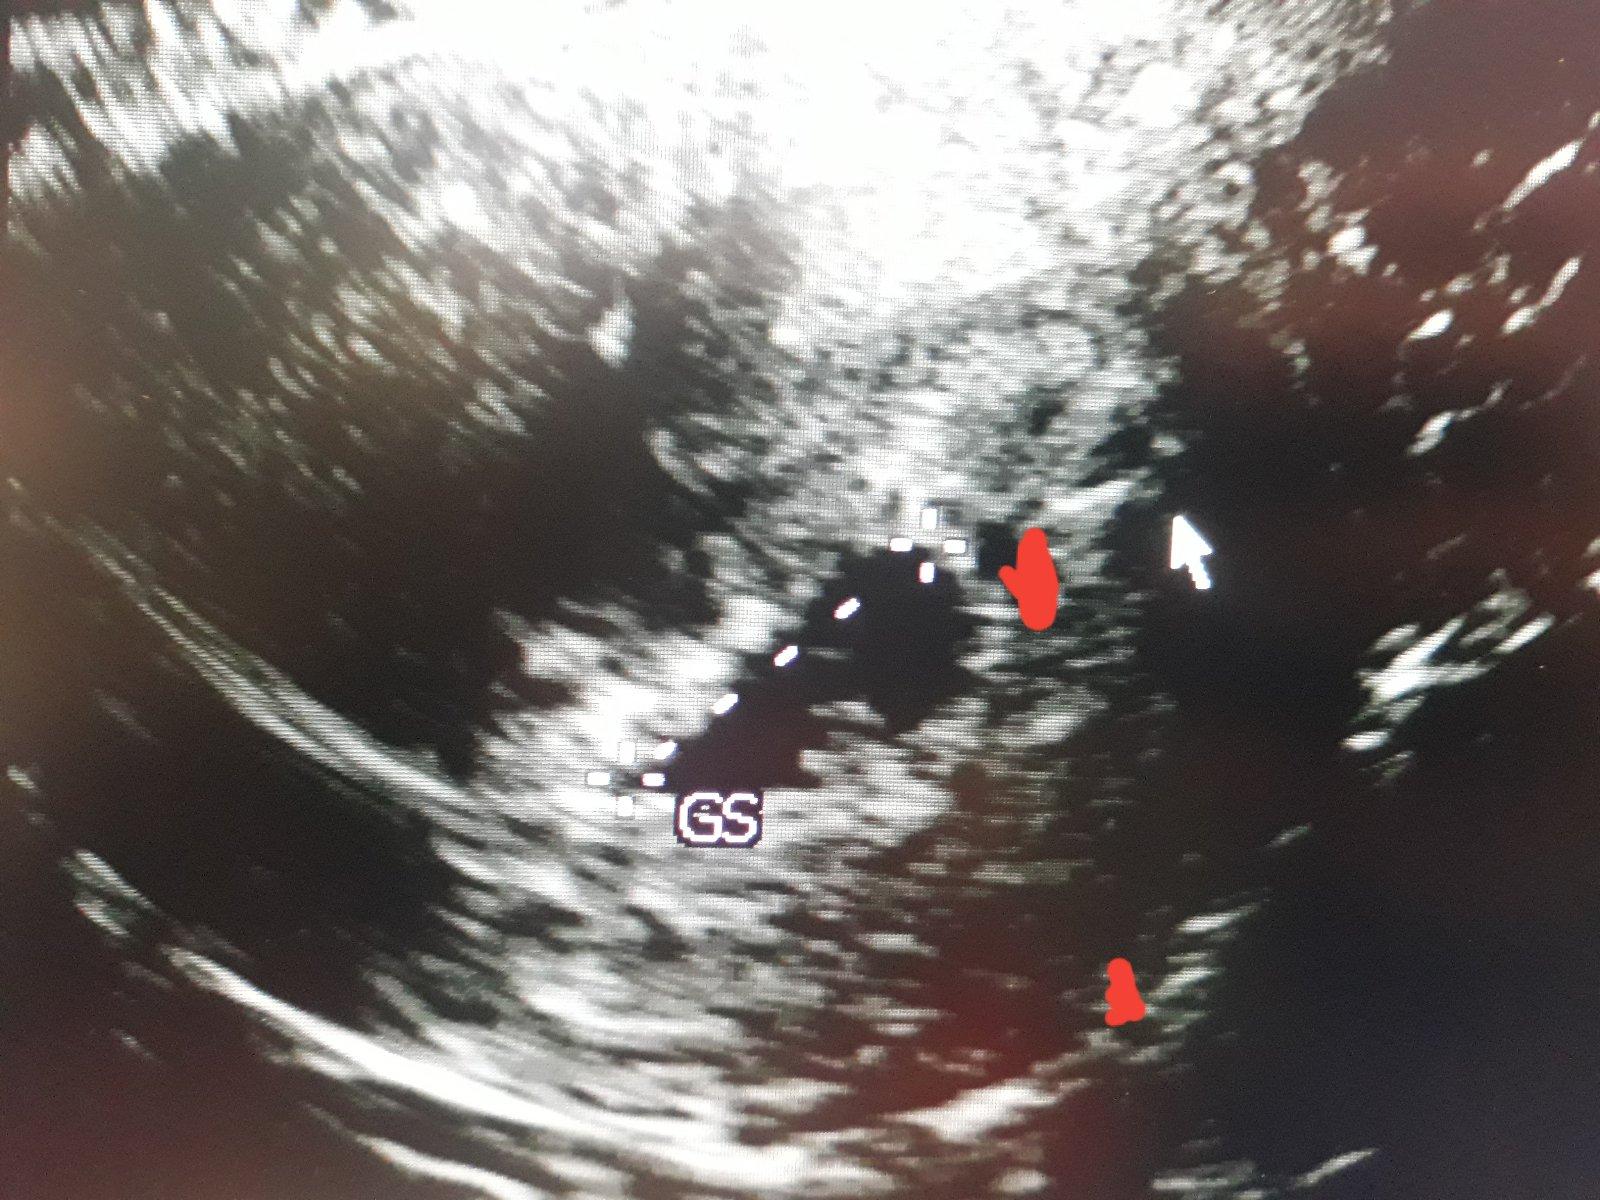

@s_lovenka cca v 6-7t